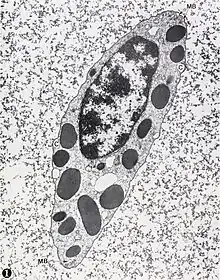

У беспозвоночных животных лейкоциты (амёбоциты) содержатся в крови, гемолимфе и полостной жидкости. Наиболее многочисленная группа фагоцитов, имеющаяся у многих беспозвоночных, — крупные базофильные незернистые амёбоциты. Они способны к амебоидному движению и демонстрируют положительный хемотаксис к чужеродным поверхностям. Фагоциты беспозвоночных подробно описал Илья Ильич Мечников. Помимо незернистых амёбоцитов, у некоторых беспозвоночных, в частности, у полухордовых, имеется система гранулярных амёбоцитов. В их цитоплазме имеются многочисленные гранулы, а также особые микротрубочковые структуры диаметром 15—20 мкм. По химическому составу гранулы можно разделить на две группы. Гранулы первой группы имеются у амёбоцитов насекомых, ракообразных, асцидий, стрекающих и, вероятно, иглокожих. Эти гранулы содержат мономеры белка, способного к полимеризации, неактивный фермент, запускающий его полимеризацию, фенолы и неактивную в гранулах фенолоксидазу, а также мукополисахаридный матрикс, поддерживающий неактивное состояние в гранулах указанных ферментов. Активация происходит во время высвобождения содержимого гранул путём экзоцитоза, при этом мономерный белок полимеризуется и формирует плёнку, которую укрепляют хиноны, образующиеся при окислении фенолов фенолоксидазой. Функции гранулярных амёбоцитов различны в разных группах животных. Так, у асцидий благодаря формированию плёнки укрепляется вещество туники, у насекомых они участвуют в закупорке отверстий в наружных покровах, у ракообразных они обеспечивают инкапсуляцию гиф паразитических грибов. Гранулы второй группы, обнаруженные у приапулид и мечехвостов, не содержат фенолов и фенолоксидазы. У этих животных гранулярные амёбоциты обеспечивают свёртывание гемолимфы и защиту от чужеродных агентов[25].